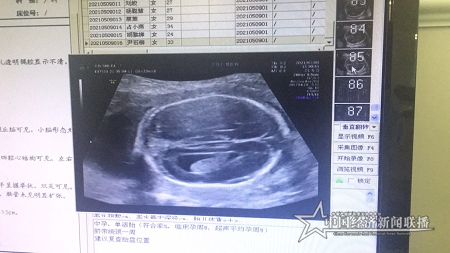

當天下午,同樣到仁愛醫(yī)院超聲科做四維彩超檢查的尹女士,也同樣檢查出了胎兒畸形。檢查時發(fā)現(xiàn),尹女士已孕育21周3天的胎兒,腦部透明隔腔消失、側腦室呈淚滴狀改變、大腦縱裂池增寬、胼胝體缺失或發(fā)育不良等畸形。

仁愛2.png

胎兒四維彩超影像